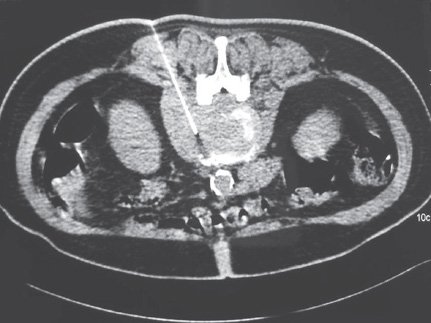

High-resolution digital imaging for detailed cellular analysis.